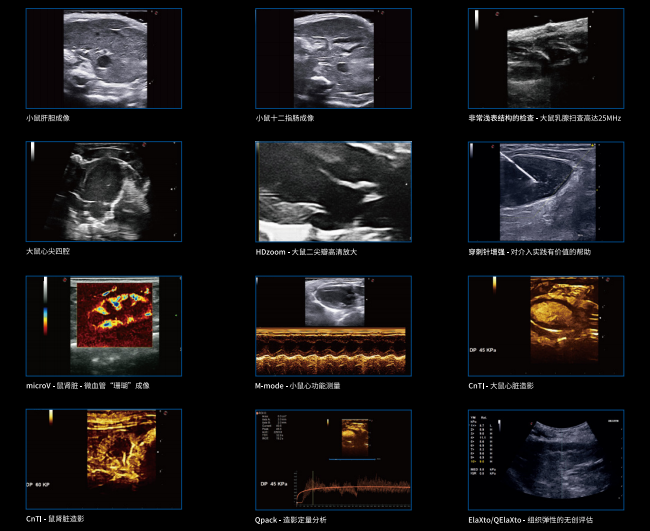

MyLabX8VET还拥有高度直观的用户界面和先进的临床工具,为用户量身定制,实现超乎想象的效果。用户可以轻松地进行多项检查和诊断,包括心脏、肝脏、肾脏、腹部、泌尿系统等。

MyLabX8VET设定了高性能的标准,提供了全新的超声体验。该设备不仅具有高品质的图像质量和丰富的功能,还可以通过网络连接实现远程协作和教学,为兽医学的教学和科研提供了支持。